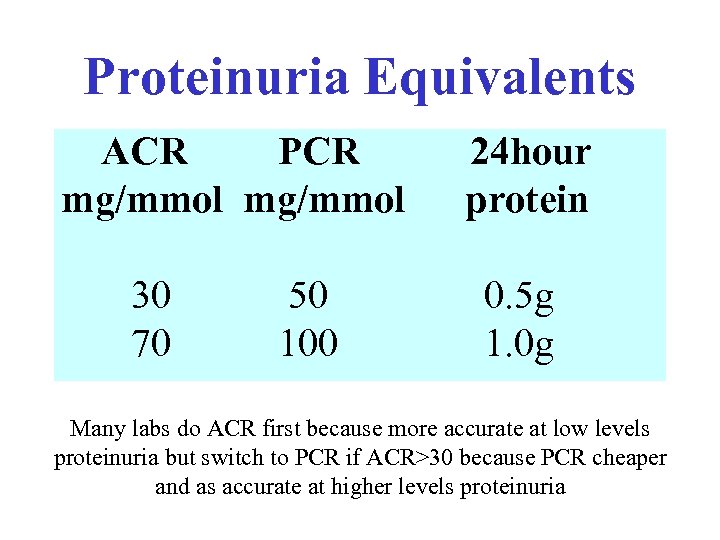

Proteinuria Equivalents ACR PCR mg/mmol 30 70 50 100 24 hour protein 0. 5 g 1. 0 g Many labs do ACR first because more accurate at low levels proteinuria but switch to PCR if ACR>30 because PCR cheaper and as accurate at higher levels proteinuria

Proteinuria Equivalents ACR PCR mg/mmol 30 70 50 100 24 hour protein 0. 5 g 1. 0 g Many labs do ACR first because more accurate at low levels proteinuria but switch to PCR if ACR>30 because PCR cheaper and as accurate at higher levels proteinuria